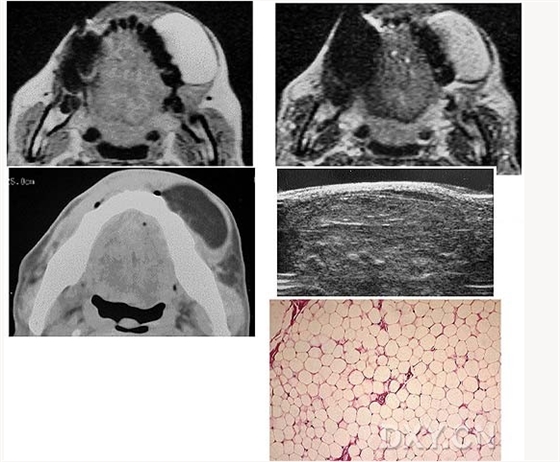

腺淋巴瘤[沃辛瘤

脂肪瘤